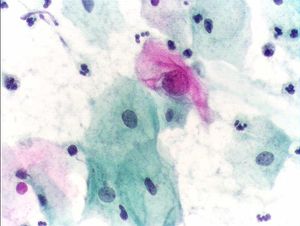

비정상적인 자궁경부 세포 검사

파파니콜라우 검사는 질경을 통해 여성의 질 내부를 관찰하여 질과 자궁경부에서 세포를 채취하여 유리 슬라이드에 도말, 현미경으로 관찰하여 자궁경부암 및 기타 세포학적 질병을 진단하는 방법이다.[1] 이 검사를 통해 암세포 및 전암세포를 조기에 발견할 수 있다.

1928년, 게오르요스 파파니콜라우는 질 분비물 검사를 통해 자궁경부암 진단이 가능하다는 것을 제시했지만, 1943년에 그와 부인과 의사 허버트 트라우트의 공저로 『질 도말 검사에 의한 자궁암 진단』이 출판되기 전까지는 일반에 거의 알려지지 않았다. 이 검사 방법은 '''파파니콜라우 검사'''('''Pap'''anikolaou '''test''')로 불리며, 현재도 자궁암 진단에 사용되고 있다. 또한, 이 당시에 개발된 염색 방법을 '''파파니콜라우 염색'''이라 하며, 이는 이후 병리 진단 기술 발전에 크게 공헌했다.[1]